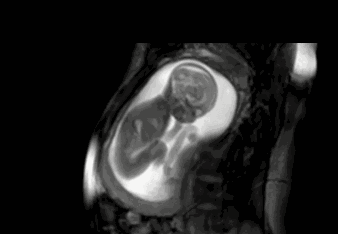

同樣的,“辰”用於“生殖”方面時,是指“卵子受精後到胎兒分娩這個過程”,為強調是“人類”,所以變成“娠”——《說文》“辰,有身也”就是指此意。

“種子萌發到破土而出長成幼苗(終見天日)“的種植過程與“卵子受精到分娩出新生兒(終見天日)”的生殖過程是不是很相似?——都是“在黑暗中不斷變化,最後實現突破,終見天日迎來光明”。